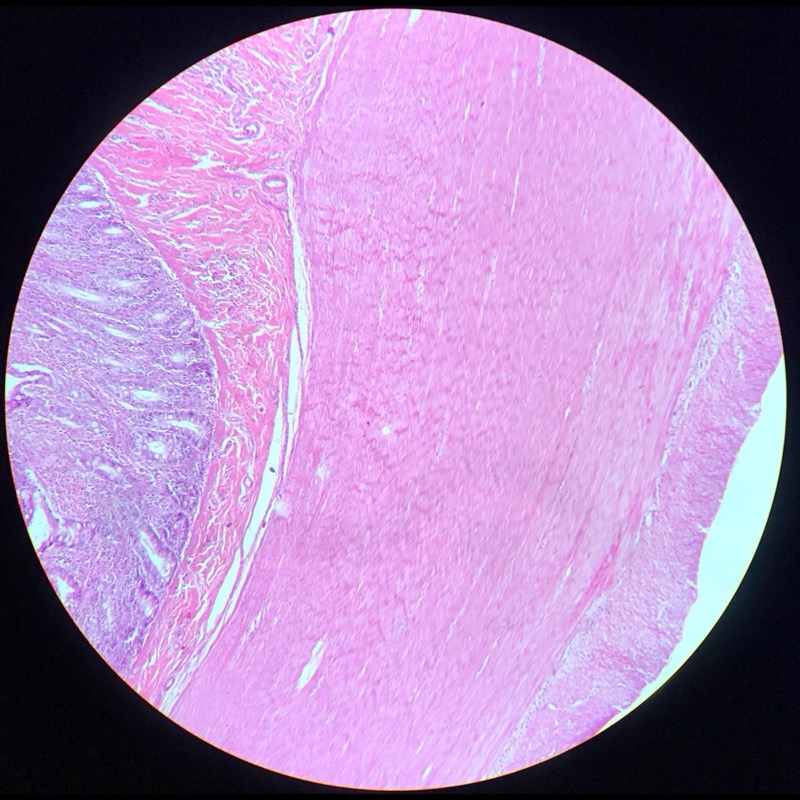

| 1:5:7 | Tjock Hud fotsula | ![]() ![]() ![]() ![]() ![]() ![]() ![]() ![]() |

| 1:5:2 | Hud med Vater Paccinis | ![]() ![]() ![]() ![]() ![]() |

| 1:5:3 | Hud Fettväv talg | ![]() ![]() ![]() ![]() ![]() ![]() ![]() ![]() ![]() ![]() ![]() ![]() |